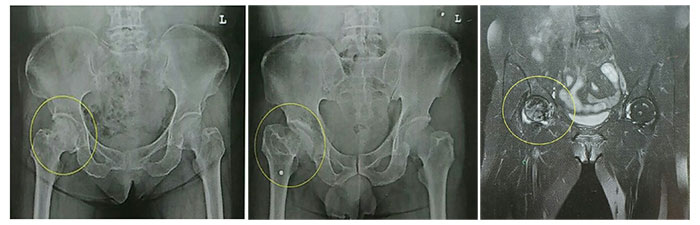

고관절 통증 증상 5.고관절의 무혈성 괴사

무혈관성 괴사란 혈액 순환 장애로 인해 혈액 공급이 원활하지 못하여 뼈가 썩는 병입니다. 대퇴골두 무혈관성 괴사는 허벅지 뼈, 즉 대퇴골의 머리 부분에 피가 통하지 않아 이 부분이 괴사 하게 되는 것입니다. 대부분 30~50대에게 발생하고, 여성보다는 남성에게 더 많이 발생합니다. 약 60% 이상은 양쪽 고관절의 대퇴골두 무혈관성 괴사를 겪습니다. 대퇴골두 무혈관성 괴사를 일으키는 위험 인자로는 음주, 부신피질 호르몬 투여, 고관절 부위 외상, 잠수병, 통풍, 혈청지질 이상, 만성 신질환, 만성 췌장염 등이 있습니다. 이 중에서도 음주와 부신피질 호르몬제가 전체 원인의 90% 정도를 차지합니다.